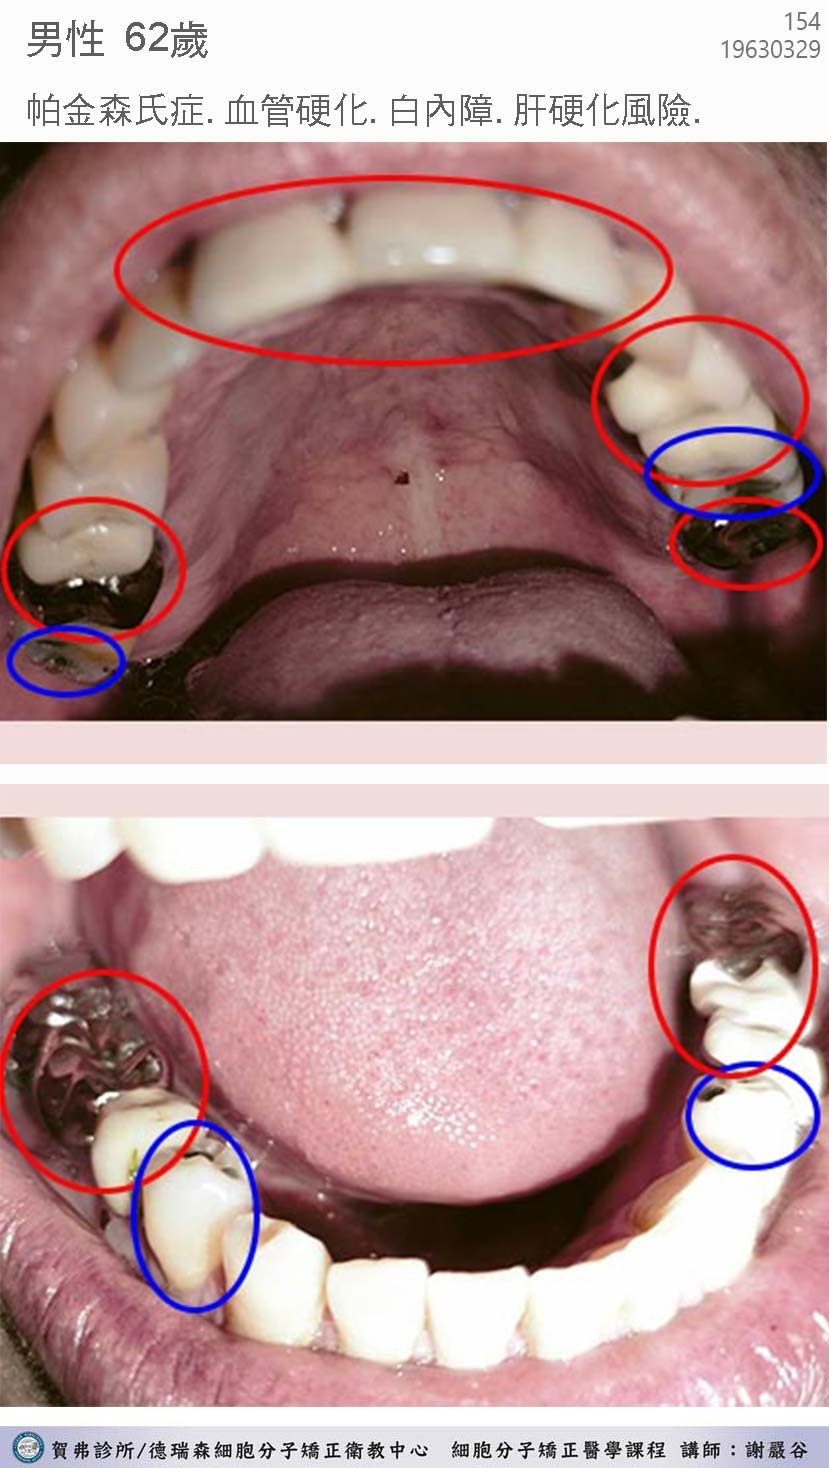

一開始賀弗診所的治療,老師就要我去除毒牙(抽神經填補銀粉)這難度太高了,因為毒牙太多了,高達九顆,而且一半在門牙,拔掉後,除了咀嚼食物問題外,又有礙觀瞻!重點是,實在很難找到牙醫師願意拔根管牙 ⋯ 當時想到這重重的困難,半信半疑的我真的很想放棄⋯

恰好此時,資深牙醫,傅醫師,也出現在課堂上,他十分熱心願意幫我的拔毒牙清理齒糟。於是二個月內,十分感謝傅醫師加班幫我密集的拔掉了9顆毒牙,拔出來的牙狀非常可怕,通報謝老師並看到死牙照片後,她非常篤定地告訴我,我的帕金森神經毒,終於找到最大的病灶了!